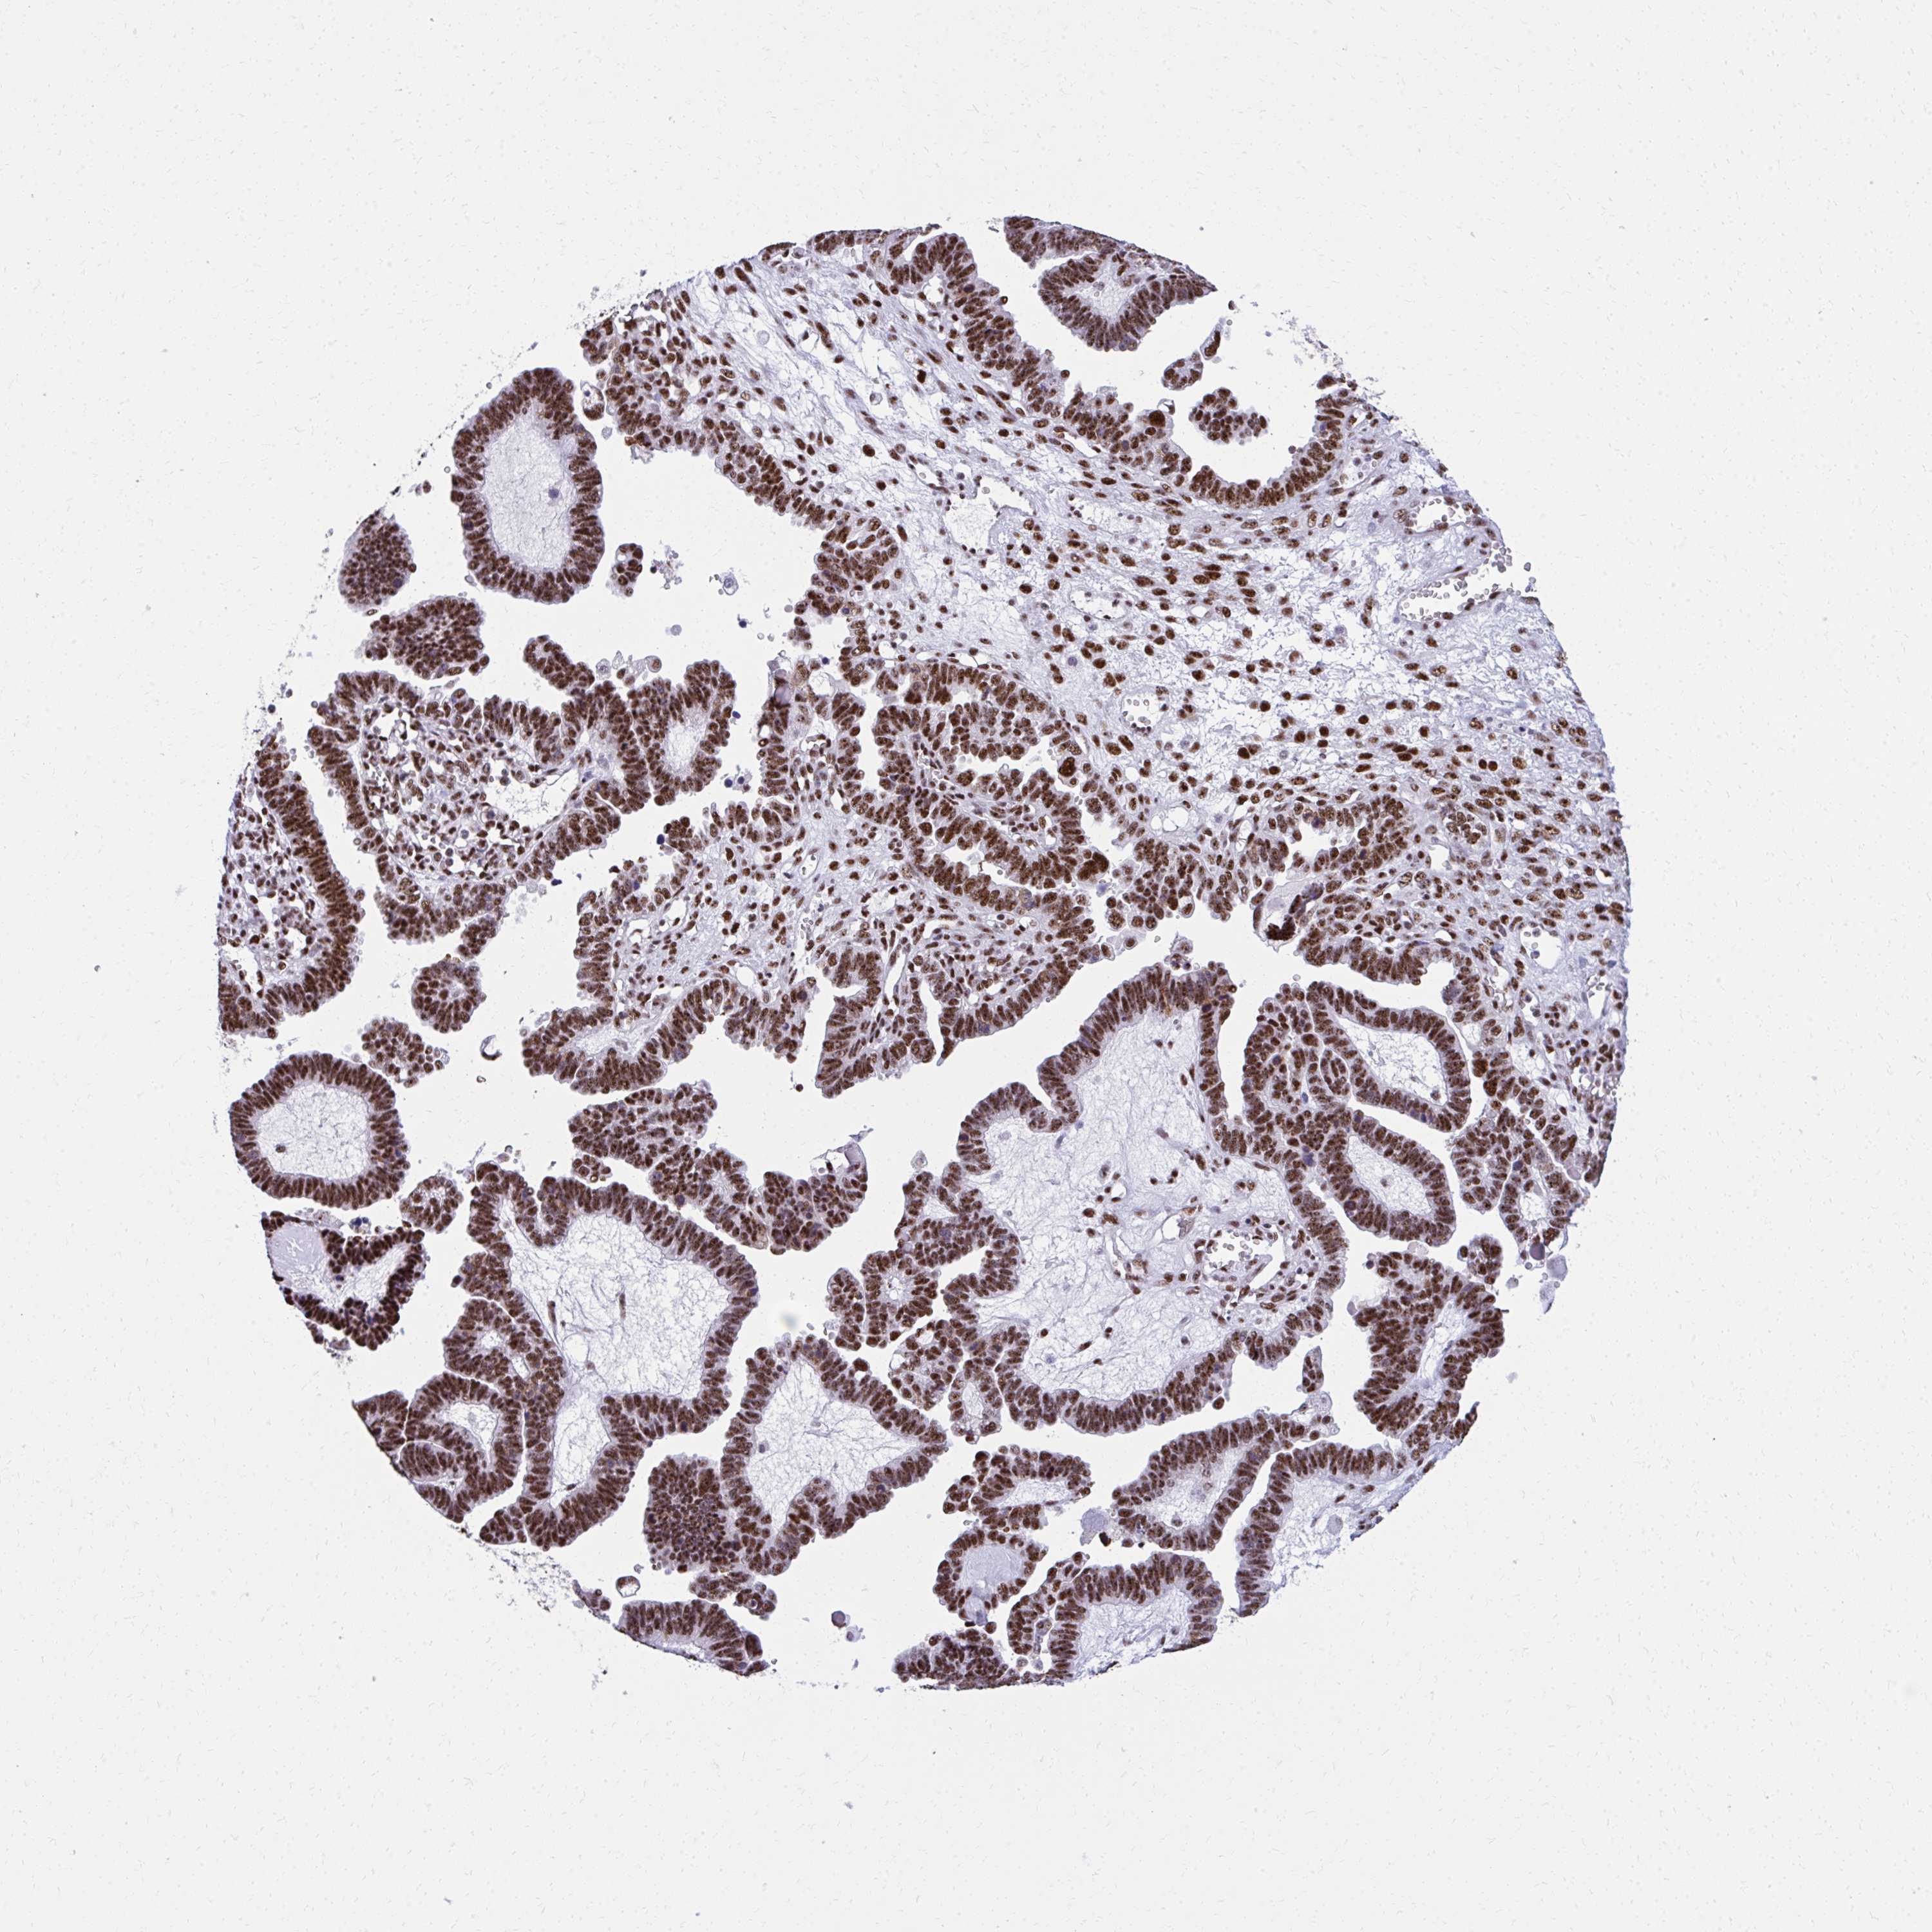

OVARIAN CANCER - Protein expressioni

A mouse-over function shows sample information and annotation data. Click on an image to view it in a full screen mode. Samples can be filtered based on level of antibody staining by selecting one or several of the following categories: high, medium, low and not detected. The assay and annotation is described here.

Note that samples used for immunohistochemistry by the Human Protein Atlas do not correspond to samples in the TCGA dataset.

Antibody stainingi

Antibody staining in the annotated cell types in the current human tissue is reported as not detected, low, medium, or high, based on conventional immunohistochemistry profiling in selected tissues. This score is based on the combination of the staining intensity and fraction of stained cells.

Each image is clickable and will lead to virtual microscopy that enables deeper exploration of all samples and also displays staining intensity scores, fraction scores and subcellular localization as well as patient and tissue information for each sample.

Antibody HPA060760

Staining

High

Medium

Low

Not detected

Intensity

Strong

Moderate

Weak

Negative

Quantity

>75%

75%-25%

<25%

None

Location

Nuclear

Cytoplasmic/membranous

Cytoplasmic/membranous,nuclear

Cystadenocarcinoma, serous, NOS

Cystadenocarcinoma, mucinous, NOS

Carcinoma, endometroid